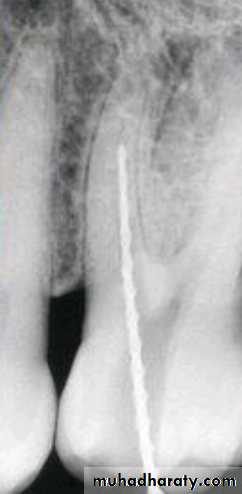

Standardized Technique

Standardized tech. Illustration